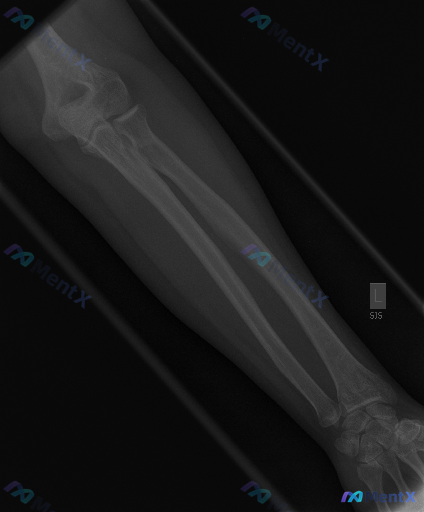

整理到一组临床+影像的资料,想跟大家讨论一下这种情况的判断思路: 基本背景:影像显示为青少年骨骼发育阶段(存在骨骺生长板)。 影像表现(左前臂正位X光): - 尺桡骨皮质连续,未见明确骨折线、脱位或半脱位; - 各关节间隙宽度尚可,关节面平整; - 前臂软组织轮廓清晰,未见明显弥漫肿胀、脂肪垫征或异...